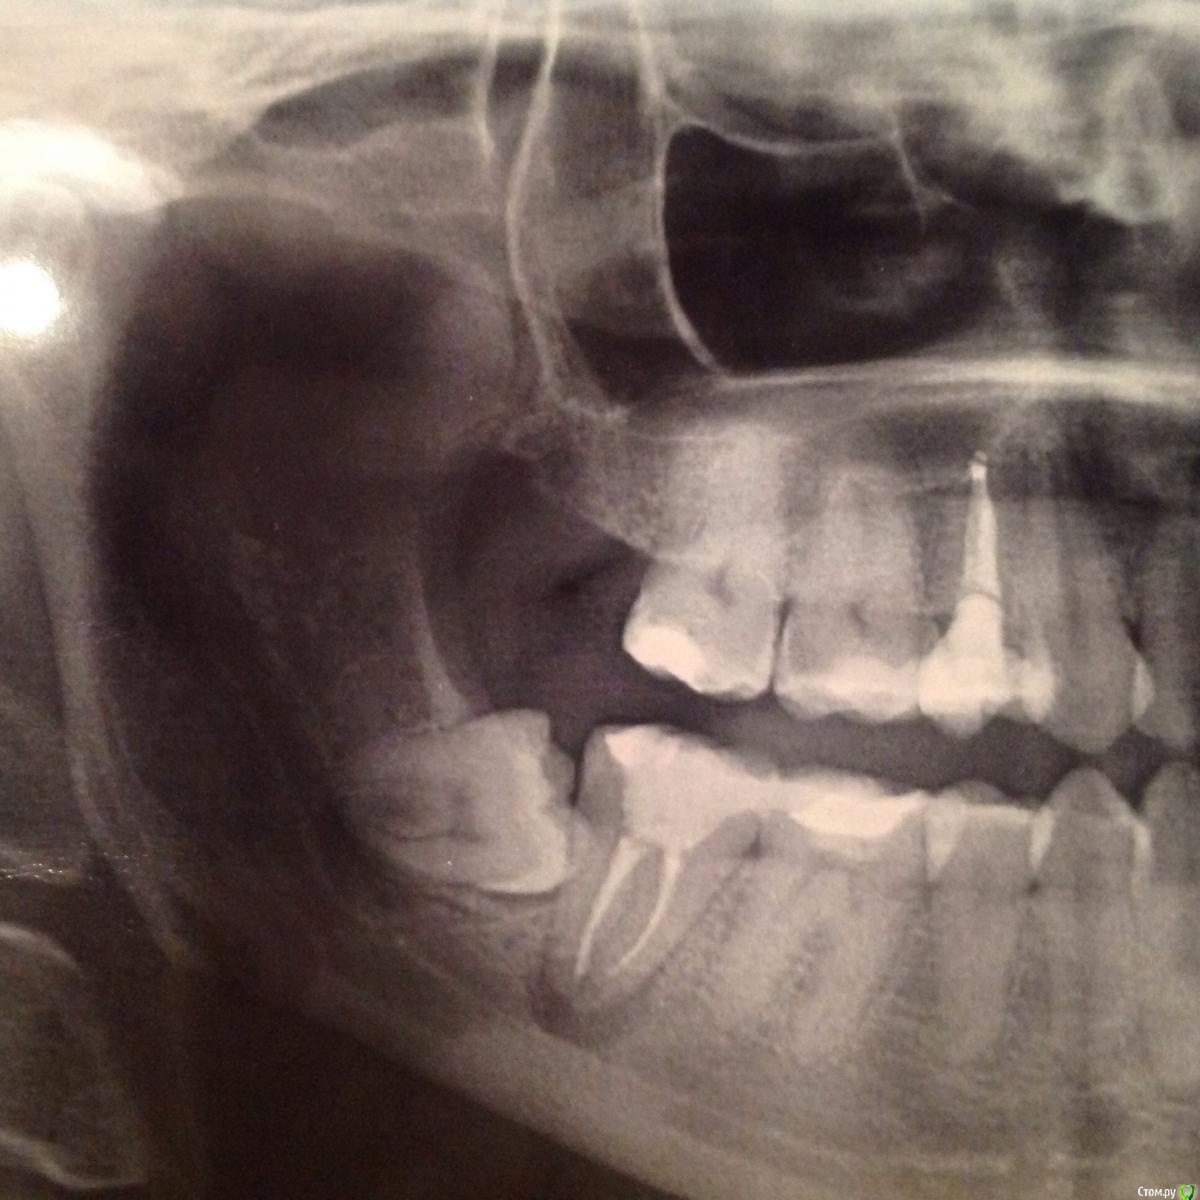

Катруся Опубликовано 30 марта, 2015 Поделиться Опубликовано 30 марта, 2015 (изменено) Добрый!Подскажите, пож-та. У меня болит нижняя семерка правая, депульпированная. Боль ноющая, при надавливании усиливается, на холод/горячее не реагирует. Каналы запломбированы несколько лет назад. Жаловалась в течение этих лет неоднократно своему врачу, но из за зуба мудрости, который лез в семерку, мы думали что болит из за него, т к после депульпирования делали снимок и каналы проверяли на качество заполнения. Зуб мудрости, который на снимке в наст момент удален (4,5 месяца). Снимку тоже 4,5 месяца. Судя по снимку у меня киста... Это я уже сейчас вижу, после того как провела собственное так сказать расследование... Врачи этот снимок видели: и хирург и мой врач-стоматолог... Ничего не сказали.... Подозревать их в некомпетентности у меня нет оснований, т к лечу у них все очень долго и вся моя семья тоже ... Но все же, бывает всякое....Подскажите, каналы запломбированы нормально? Или киста, если это киста, образовалась из за того, что они не до конца заполнены... Или она образовалась из за неверно росшей восьмерки???? Спасибо Изменено 30 марта, 2015 пользователем Катруся Ссылка на комментарий

Катруся Опубликовано 30 марта, 2015 Автор Поделиться Опубликовано 30 марта, 2015 Гарриевич, спасибо за ответ. Прикладываю ОПГ до депульпирования. По моему не профессиональному взгляду там не было такой картины. Про каффердам.... Припоминаю что нет, его я помню лишь последние несколько лет.... Ссылка на комментарий

Катруся Опубликовано 30 марта, 2015 Автор Поделиться Опубликовано 30 марта, 2015 Кстати, нашла этот старый снимок и увидела дату. Значит зуб был депульпирования в мае 2012 года. 3 года получается.... Ссылка на комментарий

Катруся Опубликовано 3 апреля, 2015 Автор Поделиться Опубликовано 3 апреля, 2015 Добрый. Пишу отчет о походе к другому врачу, может кому то интересно. Мне сделали МРТ, посмотрели все в 3d, корни (3 шт) пролечены хорошо на всем протяжении... Однако верх одного оказался загнутым, вероятно в этом проблема.... Хотя и эта врач точно сказать не может, почему такое воспаление.... Размер пораженной области 0,8 на 0,3 см. Лечить будем в 4 этапа. На первом надеемся открыть все корни за раз, все там промыт, вложить лекарство и закрыть временной пломбой на 1 мес не меньше.... Ну и там по мере лечения будем смотреть динамику... Резекция не показана, т к на снимке корни в непосредственной близости от вены ( или артерии? Что там?), которая в нижней челюсти проходит... Вот такие дела. Как схожу на первый прием - напишу как все прошло. Спасибо откликнувшимся врачам! По стоимости: пока мне примерно посчитали 36 000. Ну и плюс я уже заплатила 3500 за МРТ. Вот так вот((( учитывая что я в отпуске по уходу ребенком, эта сумма сейчас оооочень существенна для меня... Берегите зубы, ищите хороших врачей... Ссылка на комментарий